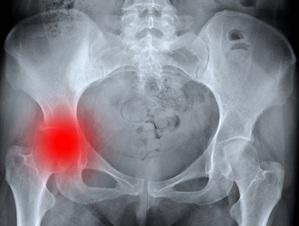

Коксартроз - это остеоартроз тазобедренного сустава. Данная патология характеризуется наличием дегенеративно-дистрофических процессов, происходящих в опорно-двигательном аппарате и приводящих к развитию деформирующего артроза тазобедренного сустава. Эта патология считается одной из самых распространённых болезней опорно-двигательного аппарата.

Диагностика

При появлении симптомов заболевание необходимо обратиться к терапевту, который на основе первичного осмотра направляет больного к ортопеду или ревматологу. Эти специалисты осуществляют клинический осмотр с замером конечностей и снимают их функциональные пробы. Диагностические обследования, которые назначаются для постановки точного диагноза заболевания:

- компьютерная томография;

- рентген;

- магнитно-резонансная томография.

— для получения точной картины назначается рентгенография обоих тазобедренных суставов. Это позволяет оценить изменение суставной щели, наличие остеофитов или других патологических изменений в суставе.